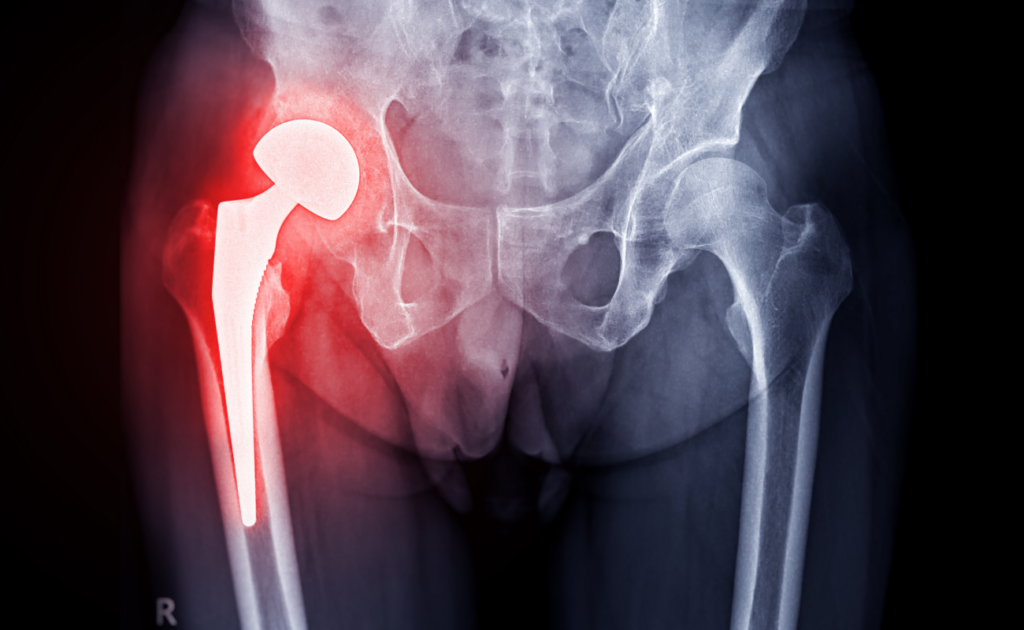

Chirurgia dell’Anca

La chirurgia dell’anca è fondamentale per trattare patologie degenerative e traumatiche che compromettono il movimento e causano dolore intenso. Il Dott. Edoardo Cristalli si specializza nel trattamento di problematiche come l’artrosi dell’anca, fratture o dislocazioni. Quando i trattamenti conservativi non sono sufficienti, la sostituzione protesica dell’anca può essere la soluzione ideale, restituendo al paziente mobilità e qualità della vita. L’approccio chirurgico viene eseguito con tecniche avanzate, minimizzando i rischi e accelerando il recupero.